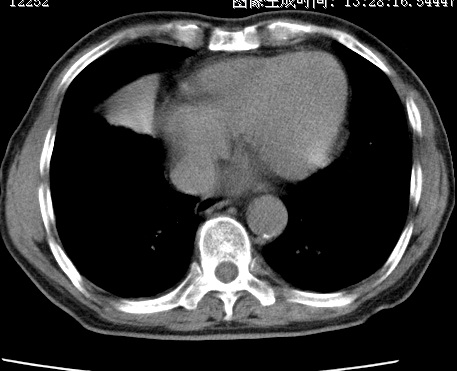

标题: CT24032:男65岁,咳嗽,吸烟20余年,无发热,咳痰 [打印本页]

标题: CT24032:男65岁,咳嗽,吸烟20余年,无发热,咳痰

考虑右肺中叶不张,请大家发表意见

右肺中叶不张、肺门轮廓增大,占位不除外;建议增强,必要时支气管镜详查。

右肺中叶支气管闭塞,中叶肺不张,右侧肺门见肿块影。中心型肺癌的可能大。建议支气管镜检查。

右中叶体积明显缩小,且其支气管未显示,先考虑:中心型肺癌班右中叶肺不张。

考虑右肺中叶中央型肺癌并右肺中叶肺不张;建议:行纤支镜检查。

右肺门旁类圆形肿块影,右肺中叶不张,建议纤支镜检查。

1右肺门旁类圆形肿块影,右肺中叶不张,建议纤支镜检查

2右侧胸膜增厚,右侧叶间胸膜区钙化

3右肺下叶小囊状透亮影考虑肺气肿